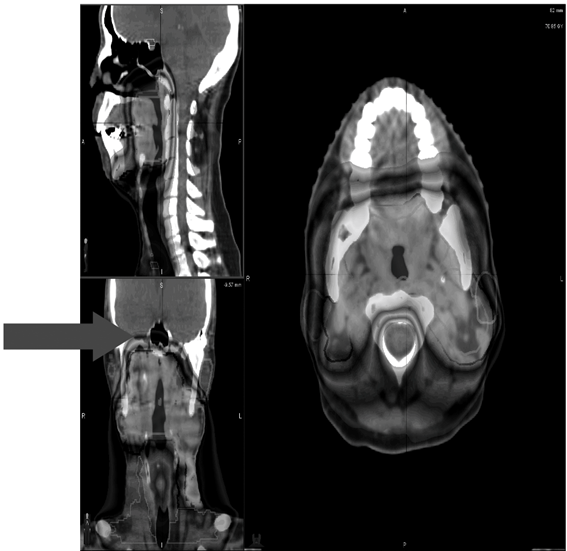

生まれのブランドで I19-175 2017年第10号10月号 臨床放射線 臨床医学